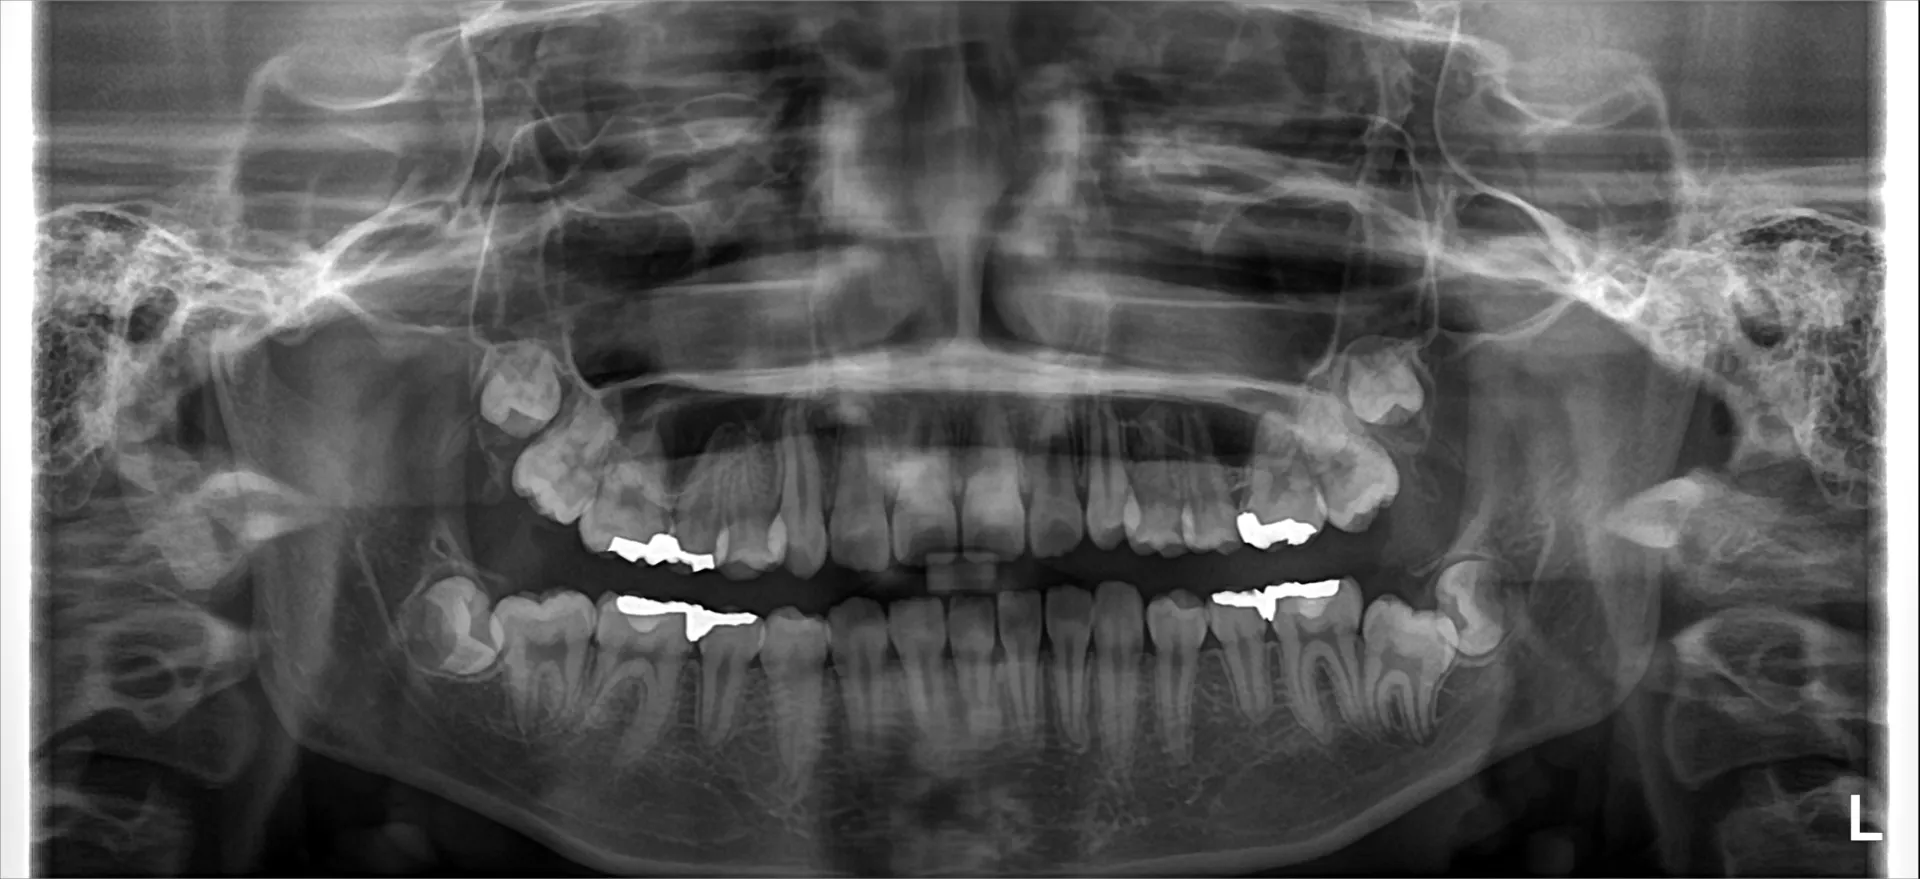

パノラマレントゲン写真

今回は12歳を過ぎても左右上下の他の歯は12歳臼歯が生えているのに左下だけが生えてこないという現象が起きた患者様でした。

原因は先ほど述べた通り親知らずが12歳臼歯に顎の中で引っかかっており、12歳臼歯が生えて来るのを阻害してしまっていました。

歯の性質上、歯の噛む面に向かって生えるという現象があるため直角にぶつかった歯同士ではお互いに生えるのを阻害してしまっています。